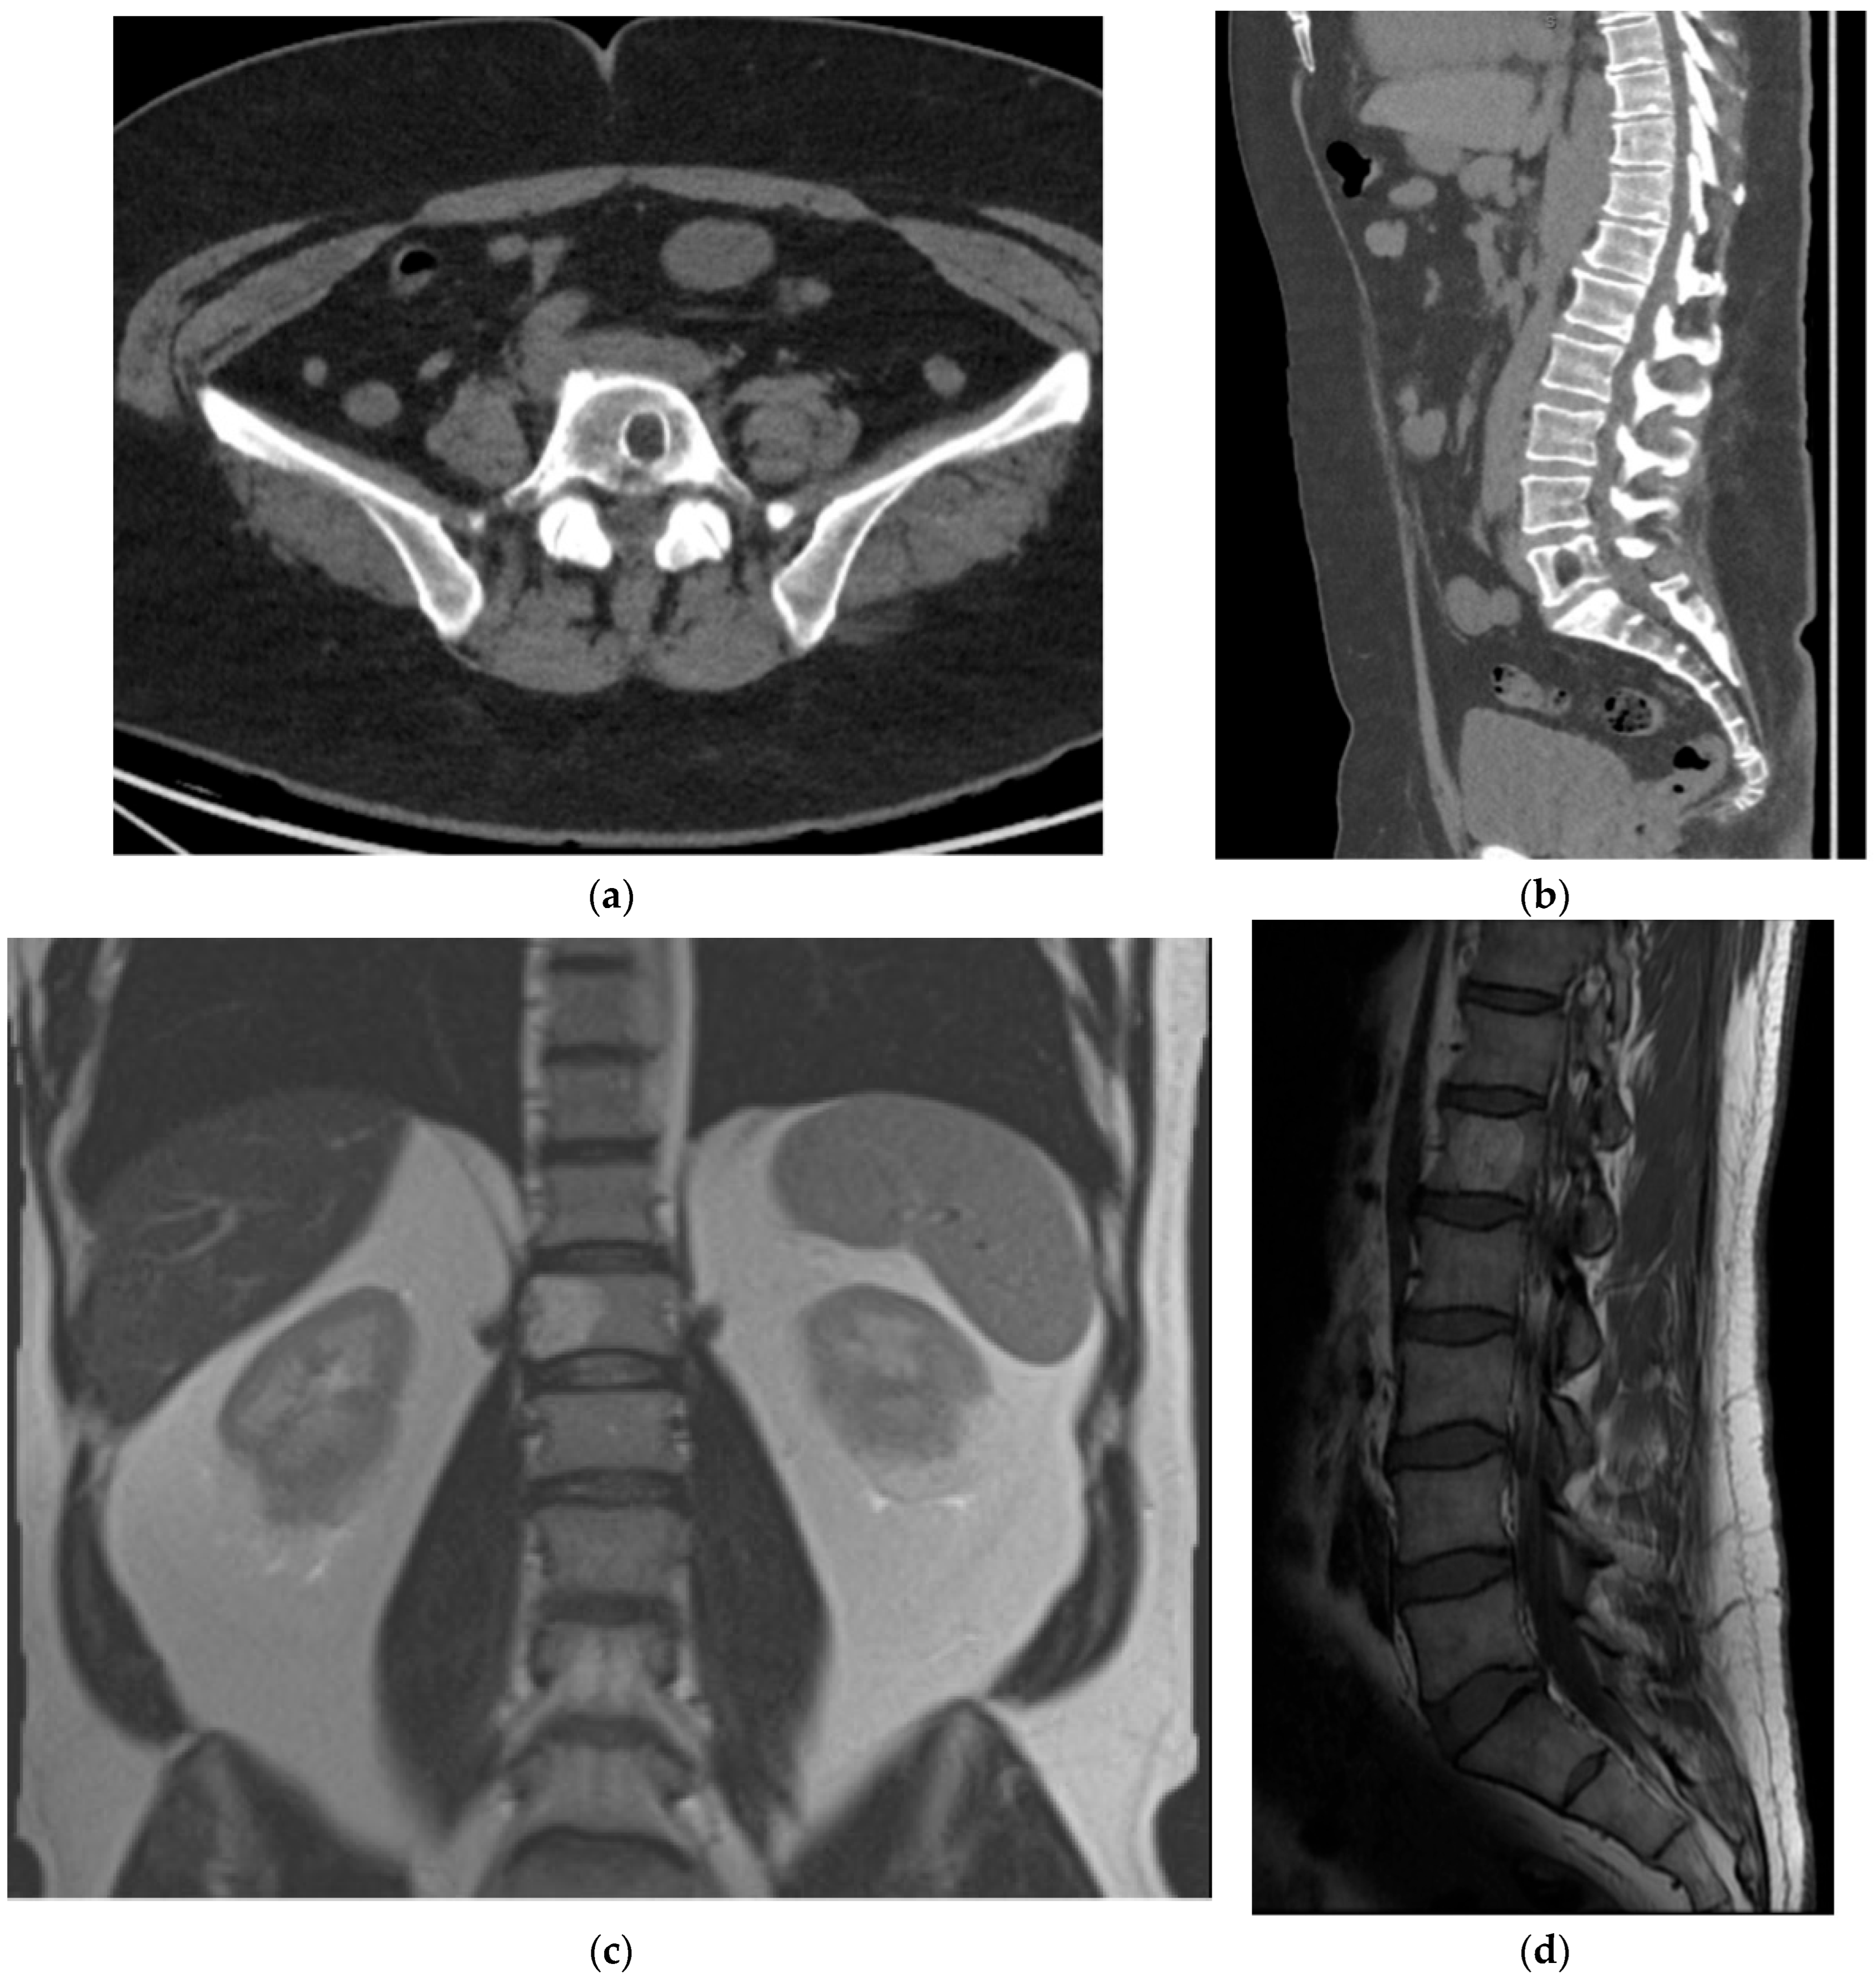

2.5.1. Hemangioma

2.5.2. Aneurysmal Bone Cyst